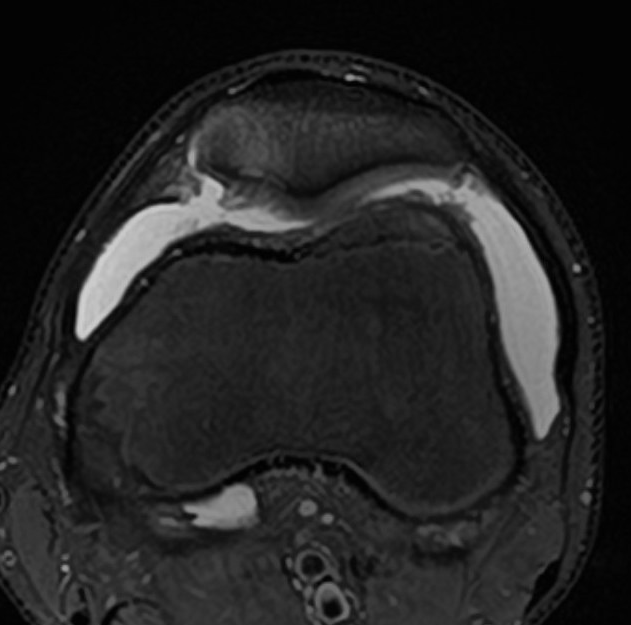

MRI